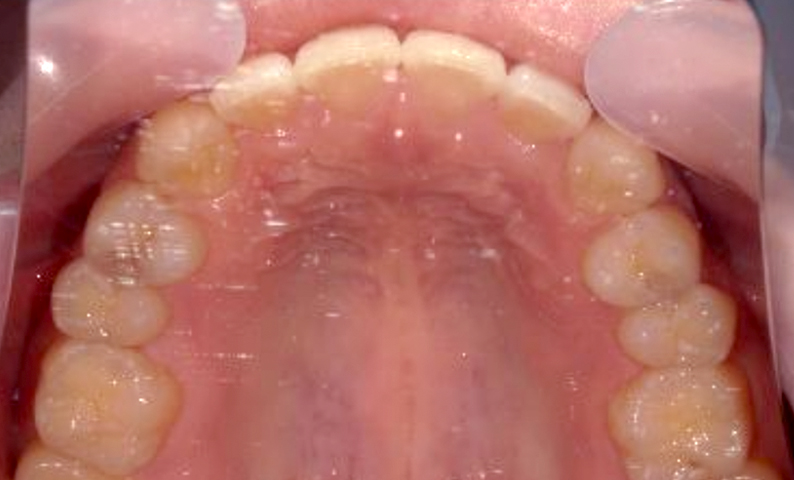

| 治療前 | 治療後 |

|---|---|

|